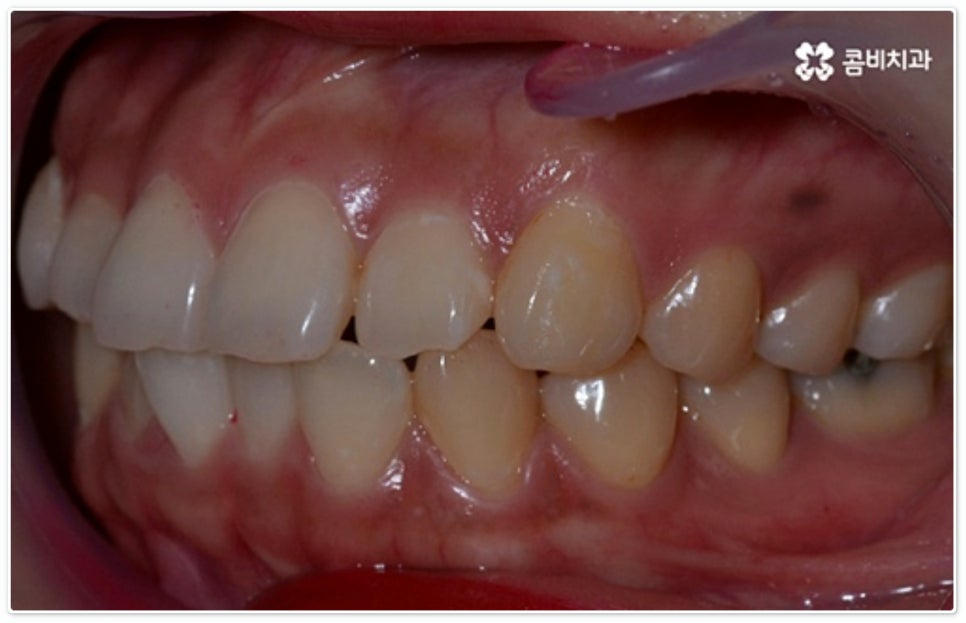

대표적으로 문제가 되는 예시로 공간이 부족하여 앞니가 앞쪽으로 튀어나온 토끼 치아, 앞니가 회전되어 나비 날개 모양으로 배열된 나비 치아 등을 들 수 있는데, 앞니는 심미성을 완성시키는 치아이므로 이로 인한 고민이 클 경우 교정 치료를 통해서 도움을 받을 수 있어요.

그렇지 않고 전후방 각도 조절 또는 단순 횡적인 움직임으로 치열 개선이 가능한 케이스는 부분 교정을 진행하는데, 사진에서 보시는 사례가 바로 그런 경우에 속하고 있습니다. 앞니 6개에만 브라켓을 부착하였는데 보시다시피 치아 색상과 유사한 세라믹 재질의 장치를 이용하여 심미성 또한 높여 주었음을 알 수 있어요.